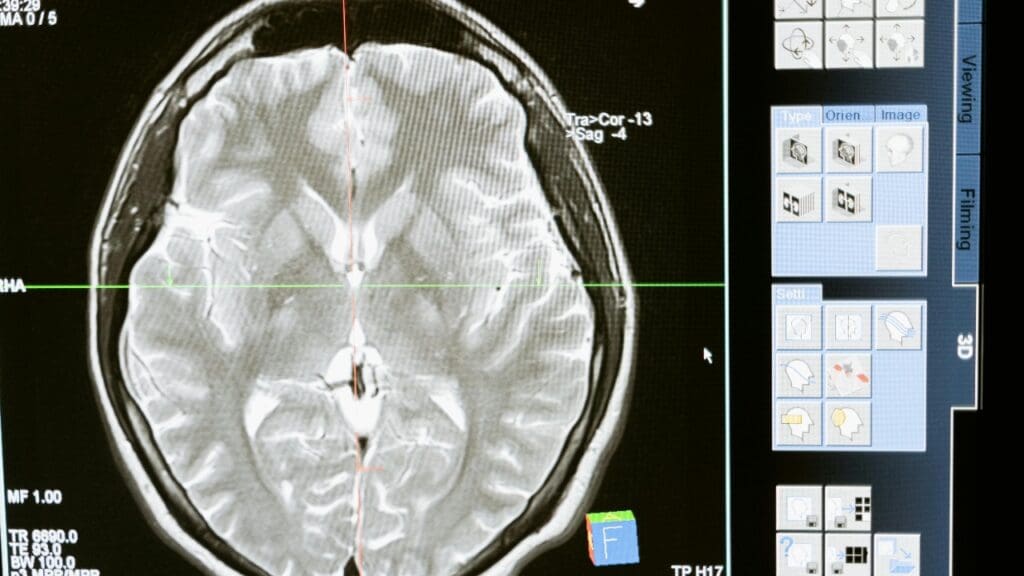

A wave of peer-reviewed research from hospitals in England and the United States shows that artificial intelligence software reading CT scans of the brain can dramatically cut the time between imaging and diagnosis for patients with life-threatening conditions such as stroke and intracranial hemorrhage. The findings, drawn from real-world clinical settings rather than controlled lab experiments, suggest that AI triage tools are already reshaping emergency radiology workflows. For patients whose outcomes depend on minutes, the speed gains documented in these studies carry direct consequences for survival and recovery.

Speed alone does not help patients if the AI introduces errors. A separate prospective evaluation published in the American Journal of Roentgenology addressed that concern head-on by measuring radiologist performance metrics, including accuracy, sensitivity, and specificity, with and without AI assistance on noncontrast head CT examinations. The study reported turnaround times for hemorrhage-positive exams alongside those diagnostic accuracy figures, providing a two-dimensional view of the technology’s clinical value. By pairing time-to-report with error rates, the investigators could determine whether AI support delivered faster care without sacrificing the quality of interpretations.

The distinction between sensitivity and specificity matters here in plain terms. High sensitivity means the system rarely misses a real bleed, while high specificity means it rarely flags a normal scan as abnormal. Both metrics need to hold up for AI triage to earn trust in emergency departments, where false alarms waste time and missed findings cost lives. The prospective design of this trial strengthens its conclusions because the AI was tested on incoming cases in real time rather than on a curated archive of past scans. That approach mirrors how the tool would actually function in a busy hospital, making the results more transferable to other institutions considering adoption and to guideline developers who rely on prospective data when weighing new technologies.